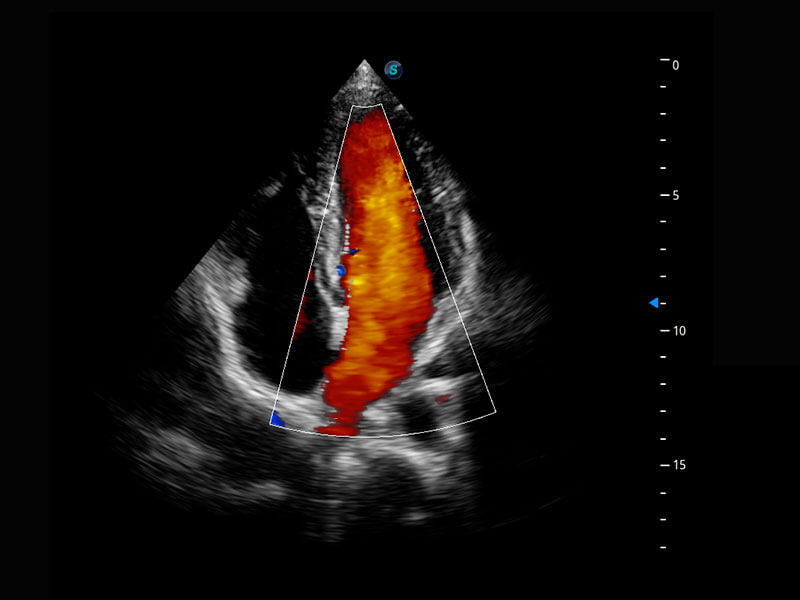

P60搭载一系列胎儿心脏成像技术,实现精细的胎儿心脏评估。

右室双出口

胎心容积成像